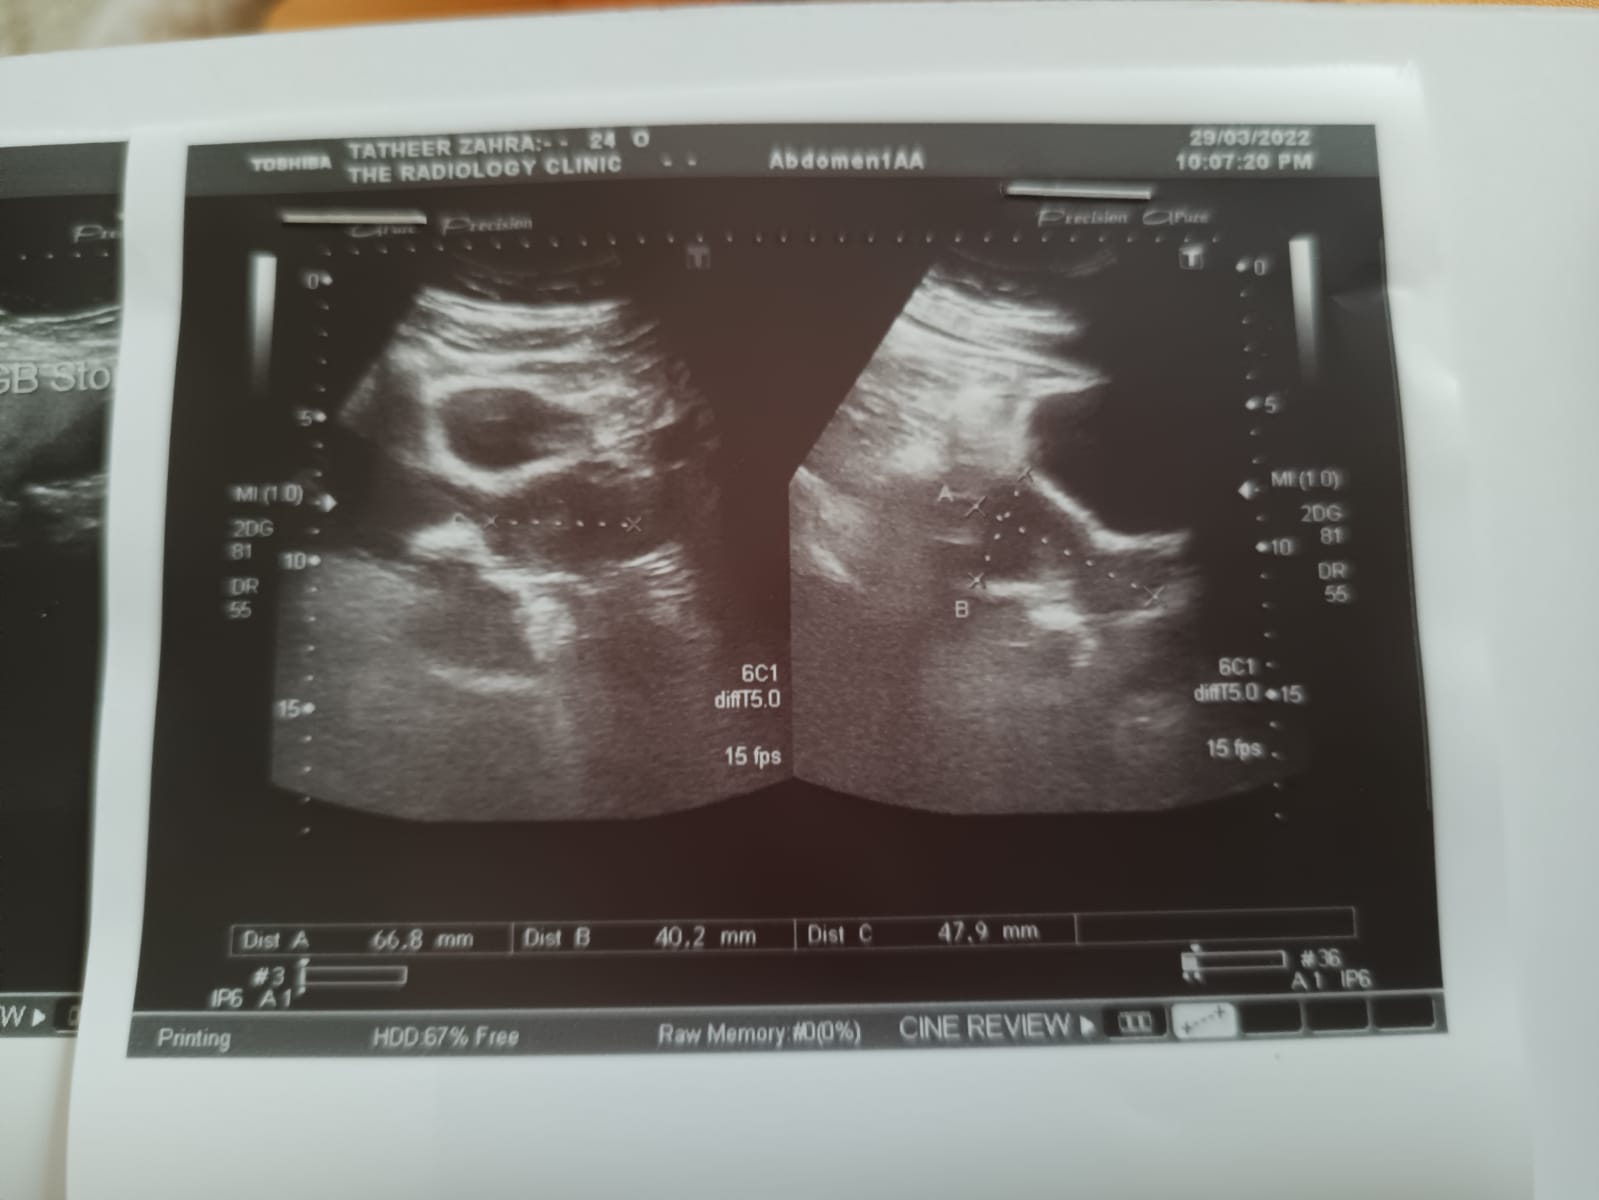

I heard that doing an operation or laser is dangerous for Gallbladder stones in the summer month like June and July because getting sweat after the operation is very dangerous is it true?